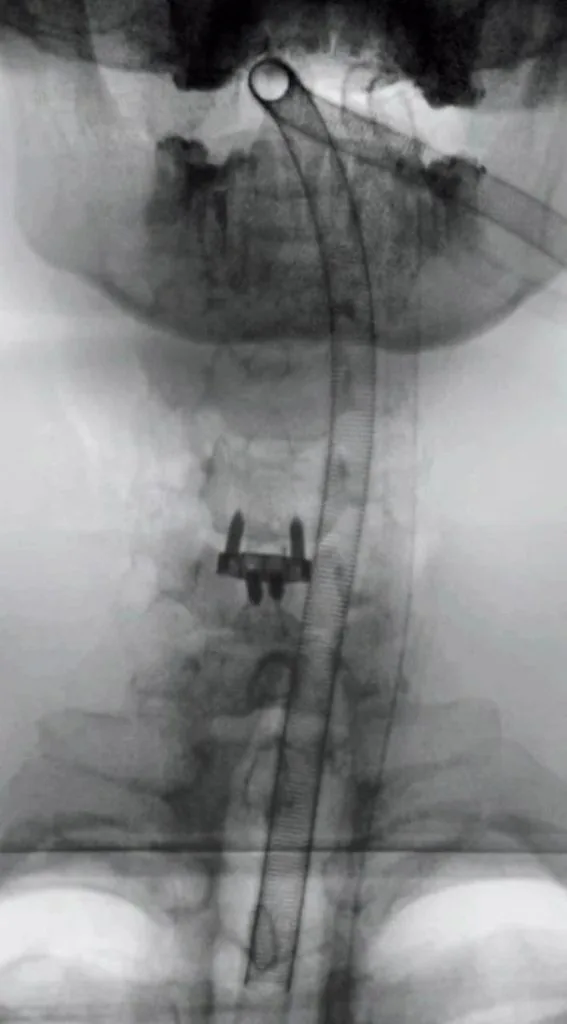

Хірургічне втручання минуло успішно — блогеру встановили спеціальний імплант у шию. Після наркозу Ніколас Карма уже вийшов на зв’язок із підписниками та показав перші кадри з операційної та одразу після під час відновлення. На шиї у нього помітний медичний пластир, однак сам блогер почувається значно краще.